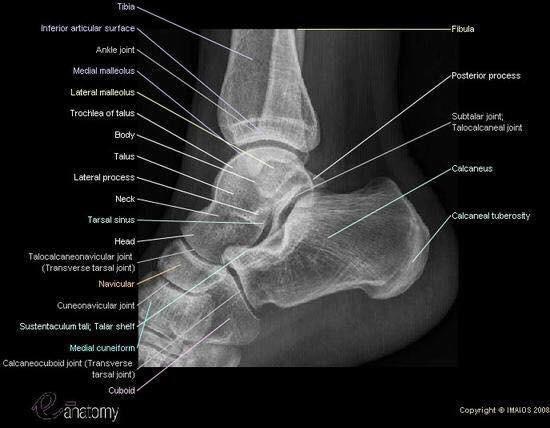

Las radiografías, generalmente llamadas rayos X, producen imágenes como sombras de huesos y ciertos órganos y tejidos. Las radiografías son muy buenas para detectar problemas óseos. Pueden mostrar algunos órganos y tejidos blandos; sin embargo, la MRI y la CT suelen crear mejores imágenes de los mismos. Aun así, las radiografías son rápidas, fáciles de obtener y menos costosas que los otros estudios, por lo que se pueden usar para obtener información rápidamente.

Un tubo especial dentro de la máquina de rayos X emite un haz de radiación controlada. Los tejidos del cuerpo absorben o bloquean la radiación en diferentes grados. Los tejidos densos como los huesos bloquean la mayor parte de la radiación, pero los tejidos blandos, como la grasa o los músculos, bloquean menos radiación. Después de pasar por el cuerpo, el haz alcanza una pieza de un fragmento de película o un detector especial. Los tejidos que bloquean altas cantidades de radiación, como los huesos, aparecen como áreas blancas en un fondo negro. Los tejidos blandos bloquean menos radiación y aparecen en tonos de gris. Los órganos que contienen principalmente aire (como los pulmones) aparecen en negro. Los tumores son por lo general más densos que el tejido que los rodea, por lo que suelen verse en tonos grises más claros.